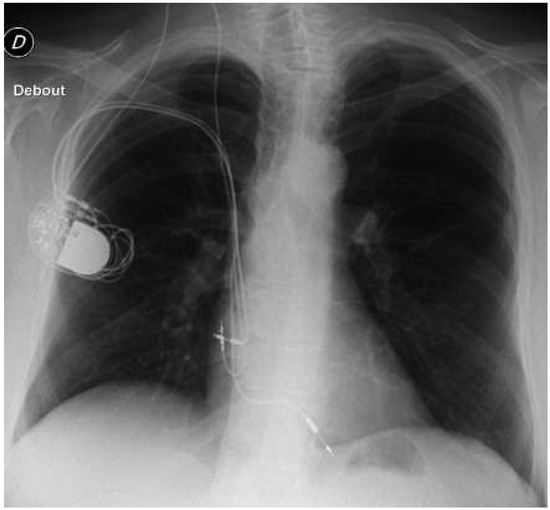

To Explant, or Not to Explant, That Is the Question

by Simon von Gunten, Jean-Luc Crevoisier, Michael Kühne, Tobias Reichlin, Stefan Osswald, Christian Sticherling and Beat Schaer

Cardiovasc. Med. 2016, 19(9), 237; https://doi.org/10.4414/cvm.2016.00424 - 21 Sep 2016

Recurrent surgery in device patients carries a certain risk of infection and should therefore be kept to a minimum. We present the case of a patient in whom a new pacemaker had to be implanted from the left side and the question was, [...] Read more.

Recurrent surgery in device patients carries a certain risk of infection and should therefore be kept to a minimum. We present the case of a patient in whom a new pacemaker had to be implanted from the left side and the question was, what should be done with the redundant pacemaker on the right side: to explant or not to explant? The answer depends upon the behaviour of the pacemaker at the time of elective replacement indication (ERI) and of end of life (EOL), and dif fers between the five manufacturers operating in Switzerland. This behaviour is explained in detail and thus can guide cardiologists towards individ ual decision making. Full article